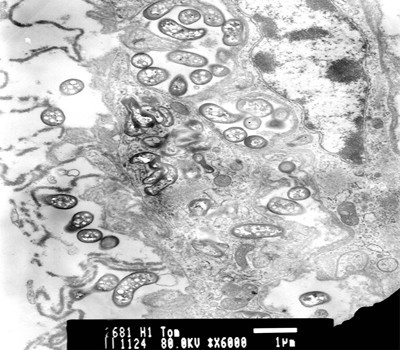

Mẫu máu soi tươi nhuộm Giemsa

Mẫu cắt mô gan tụy chụp bằng kính hiển vi điện tử

Mẫu cắt mô gan tụy nhuộm H&E

Điều đáng lưu ý là trong quá trình nghiên cứu, “đội đặc nhiệm” đã nhận được nhiều tài liệu của tổ chức thú y thủy sản thế giới phân tích một số bệnh thường gặp ở tôm hùm, nhưng chưa có tài liệu nào nói đến bệnh tôm sữa. Theo ông Nguyễn Tử Cương, sau hơn 1 tháng tập trung nghiên cứu, tháng 11-2007, lần đầu tiên các nhà khoa học Việt Nam đã tìm ra vi khuẩn gây bệnh sữa trên tôm hùm. Kết quả phân tích của nhóm nghiên cứu trong nước hoàn toàn trùng khớp với các nhà khoa học nước ngoài, 80% mẫu bệnh phẩm được xét nghiệm đều xuất hiện 1 loại vi khuẩn ký sinh nội bào, hình cong, thuộc họ Rickettsia. Hiện công tác nghiên cứu trong phòng thí nghiệm và ứng dụng điều trị tôm hùm bệnh tại lồng đang được tiếp tục tiến hành sâu hơn nhằm xác định rõ loài vi khuẩn gây bệnh và phác đồ điều trị.